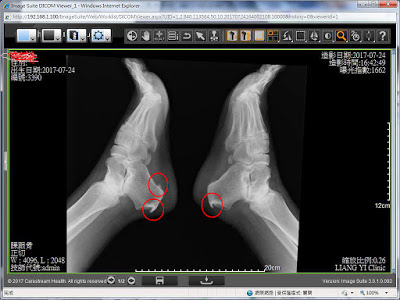

4. 跟骨骨刺

後期也可能產生鈣化、新生骨生成(俗稱骨刺)